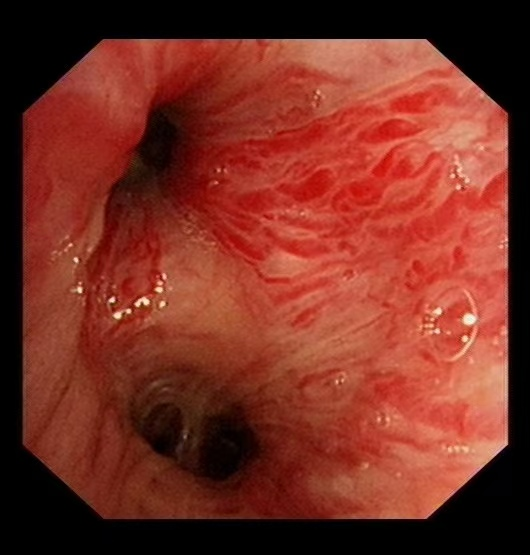

近日,一位反复腹痛、黑便的患者来到消化内科就诊,既往曾多次行胃、肠镜检查及腹部CT检查后未能明确病因,怀疑病变位于小肠,且患者由于年龄大,麻醉风险高,不宜行小肠镜检查,难道只能坐以待毙吗?此时“胶囊内镜”可派上大用场!